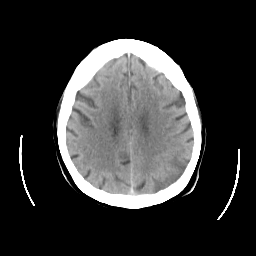

CT Study #2 -- Slice #20